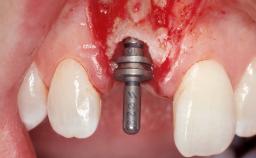

Late Flapless Placement of an Implant in a Maxillary Left Central Incisor Site

A 39-year-old male patient presented with a chief complaint of discomfort and gingival discoloration around his maxillary left central incisor. He was in good general health and was a non-smoker. His past dental history was significant because of the traumatic fracture of tooth 21 in a sporting accident at age 13. Initial dental treatment included endodontic therapy and a full-coverage restoration. The patient became symptomatic 5 years later, when structural failure of the tooth resulted in the dislodgment of the crown. Endodontic retreatment, apical surgery, and post-and-core restoration were performed.

| # of Implants | 1 |

| Attachment | One-Piece |